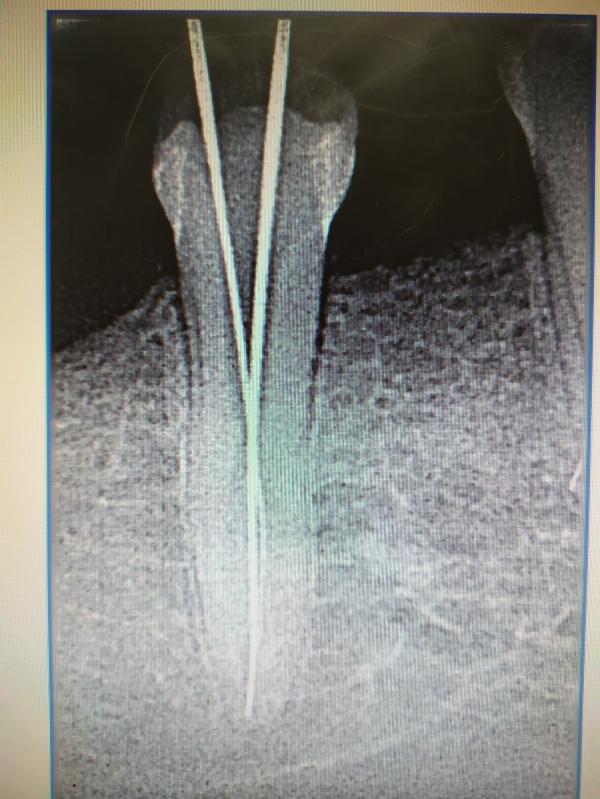

Девчонки, я снова про стоматологию, но только уже про взрослую. Вчера свердили зуб, оказался сложный с нижним раздвоением канала, доктор отказался лечить, сказал нужен микроскоп. Так вот теперь ищу клинику с микроскопом.Кто сталкивался, может знаете такие клиники?

В принципе не дорого. Попробую позвонить, спросить. У меня один канал нерв удалён, до второго канала врач не смог добраться

Лекарством закрыл каналы, пока не болит, но делать нужно в максимально ближайшее время, чтоб зуб не потерять